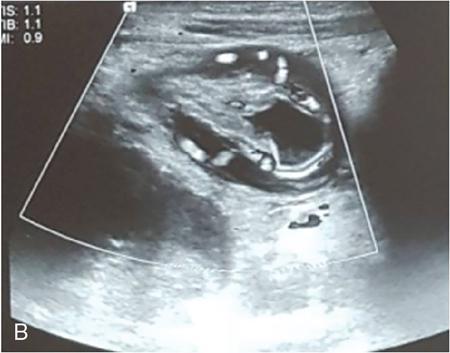

Rashmi Dixit, Anju Garg Abdominal masses are a common clinical problem in children, arising from virtually any abdominal organ. Masses arising from the gastrointestinal (GI) tract are not uncommon. They may be congenital or developmental, inflammatory, infective, idiopathic or neoplastic in nature. A high index of suspicion is necessary so as to ensure an early diagnosis and appropriate management. Imaging, therefore, plays a vital role in identifying the location, nature and extent of the mass lesion. Ultrasound (US) is the first-line imaging method for GI masses, like for most paediatric abdominal masses. It does not require sedation and is nonionizing which are important considerations in the paediatric population. US findings may be diagnostic in certain masses when no further imaging is required. Computed tomography (CT) plays an important role in complete evaluation of GI masses especially where US is either not diagnostic or the full extent and nature of the mass needs to be delineated, especially prior to surgery. It requires the administration of intravenous contrast and preferably oral contrast as well. Sedation may be required and it carries the risk of radiation exposure. Each study, hence, needs to be tailored to answer the clinical question at hand, while ensuring the lowest possible radiation exposure. Magnetic resonance imaging (MRI) provides excellent contrast resolution, which along with its nonionizing nature makes it a very attractive imaging technique. However, due to the relatively long imaging time requiring sedation, sensitivity to motion both respiratory and bowel and limited availability it is generally used as a problem-solving tool. Plain films and contrast studies currently have a very limited role in the evaluation of GI masses. Plain films may be diagnostic in masses like teratomas, while contrast studies may be required for mucosal abnormalities and small endoluminal masses like polyps. Enteric duplication cysts can occur along any portion of the GI tract from the pharynx to the rectum. They are found most often in the ileum (33%). The other sites are the oesophagus (20%), colon (13%), jejunum (10%), stomach (7%) and duodenum (5%). The incidence is reported to be around 0.2% of all children, with a slight male predominance. Duplication cysts are thought to arise between the 4th and 8th weeks of development; however, their aetiology is unknown and several different theories have been proposed. In 16%–26% cases there may be associated spinal defects, cardiac or urinary malformations. Other associated GI anomalies may be seen in about 10% of cases. Duplication cysts typically lie along the mesenteric border of the gut. They have smooth muscle wall which they share with the adjacent gut, as also the blood supply. On histopathology, three classical features are seen: an epithelial lining with GI mucosa, a smooth muscle covering and a close attachment to the GI tract due to a shared common wall. Although the mucosal lining does not necessarily match with the adjacent portion of the gut, nonetheless, duplications are named after the portion of the gut to which these are closely related. About 20%–30% of these duplication cysts contain ectopic gastric mucosa which is more common in oesophageal and small intestinal duplication cysts. Ectopic pancreatic mucosa may also be seen, most often in gastric duplication cysts. Morphologically they may be cystic or tubular with the former accounting for 80% and the latter for 20%. While cystic duplications mostly do not communicate with the adjacent gut, tubular duplications that run parallel to the GIT often do, hence in these cases connection with GIT must be demonstrated for operative planning. Duplication cysts may be multiple in 1%–7% of cases usually occurring in the same segment of the GIT. An atypical duplication cyst is an isolated duplication cyst which is completely separated from the GIT and has no communication or shared wall with the gut. They are extremely rare and thought to be the result of a vascular injury. Although duplication cysts may remain asymptomatic till adulthood they mostly present within the first year (70%). Almost 85% present by the second year. Clinical features depend not only on the size and location, but also on the presence of any ectopic mucosa and complications. Pharyngeal and oesophageal cysts may present with respiratory distress or dysphagia. Infection and rapid growth may cause retrosternal pain or haemoptysis. Gastric and intestinal duplications cause nonspecific symptoms like recurrent abdominal pain nausea, vomiting, distention or a palpable lump. High pressure inside the cyst consequent to accumulation of secretions is thought to be responsible for the recurrent abdominal pain. Obstruction due to intussusception or extrinsic compression may occur. Presence of gastric mucosa is associated with complications like inflammation, bleeding, ulceration and perforation. US is most useful for the diagnosis of abdominal duplication cysts and sometimes may demonstrate these on an antenatal scan. MR and CT are mainly used for oesophageal duplication and for planning surgery. Endoscopic trans oesophageal ultrasound may be informative for oesophageal duplications but is not a part of routine practice. Classical US features in uncomplicated duplication cysts include: a unilocular cystic structure in close proximity to the bowel. The cyst has a relatively thick wall which has a hyperechoic inner lining representing the mucosa and an outer hypoechoic rim produced by the smooth muscle layer (muscularis propria) – the so-called ‘gut signature’ sign. This sign is also referred to as the ‘double-wall’ or ‘muscular rim’ sign. (Fig. 7.7.1) Though, most characteristically described for duplication cysts, it may sometimes be seen in some other cystic lesions such as a complicated mesenteric cyst, Meckel’s diverticulum or torsed ovarian cyst. Some US signs described recently are: the ‘five layered cyst wall sign’ and ‘Y configuration of the muscle wall sign’. It has been shown that with the use of high frequency US transducers (12–18 MHz) the wall of the duplication cyst can demonstrate the same five layered wall structure as the normal GIT. From inside to outside these are: the innermost mucosa which is hyperechoic, muscularis mucosa (hypoechoic), hyperechoic submucosa, hypoechoic muscularis propria and the outermost serosa which is hyperechoic. If all these five layers can be identified in a cyst it is diagnostic of an enteric duplication cyst; however, the sign is difficult to demonstrate (Fig. 7.7.2A and B). The second sign arises because a duplication cyst shares its wall with the adjacent gut. Splitting of the common muscularis propria between the cyst and the adjoining bowel loop results in the Y configuration of the muscle layer on US, reflecting one of its important histological features. When this is seen, it is possible to confidently diagnose an enteric duplication cyst as this sign has not been demonstrated in other cysts. The ‘Y configuration sign’ can be particularly valuable in complicated cysts In addition, since US is a real time examination it also allows visualization of peristalsis of the cyst wall which is seen as a transient change in the cyst shape and contour due to contraction of the cyst wall (Fig. 7.7.3A and B). This requires the transducer to be kept stationary over the cyst for some time Most duplication cysts are anechoic but some echoes due to mucinous fluid or septations can be seen at times, and do not imply complications. Complications include haemorrhage (due to ectopic gastric mucosa), enzymatic destruction of the mucosal lining, inflammation (due to ectopic pancreatic tissue) and infection. In these cases, fluid levels or echogenic debris can be seen within the cyst with a thick hypervascular wall which may lack layers (see Fig. 7.7.2B). In these cases, the Y configuration sign can help to suggest the correct diagnosis. The inflammatory changes may extend to the surrounding mesenteric fat as well, which becomes hyperechoic. Duplication cysts near the ileocecal valve, can act as a lead point for intussusception. Atypical or isolated duplication cysts, may just produce the pseudokidney sign. The important US features of duplication cysts are listed in Box 7.7.1. Key Ultrasound Signs of Duplication Cysts CT is not performed for the diagnosis of duplication cysts, however, it can demonstrate the location, anatomical relationships, exact extent and the associated anomalies. On CT evaluation a cystic mass closely related to the adjoining GI wall is seen. The wall shows mild enhancement. A complicated duplication cyst showing internal high attenuation, air foci, thick enhancing wall and surrounding inflammation suggests infection (Fig. 7.7.4A and B). Internal high attenuation alone, however, could be due to proteinaceous contents or haemorrhage and does not imply infection on its own. MR is also not generally used as a diagnostic tool due to long examination times requiring sedation but is especially useful to demonstrate the cystic nature of thoracic duplications. Duplications cysts show hypointense signal on T1W sequences and very high signal on T2W images. Both CT and MR may be used prior to surgery. MR may have an additional value in assessment of foetal abdominal cysts. Differential diagnosis includes other cystic lesions such as mesenteric, omental, ovarian and choledochal cysts. In patients with an antenatal diagnosis, although the optimal time for resection is not defined, it is suggested that early resection within the first 6 months be considered. Treatment of asymptomatic duplication cysts remains controversial, however, since early elective surgery is associated with less morbidity and a shorter hospital stay than excision in symptomatic cases, it should be preferred. In addition, complications such as obstruction or massive bleeding may be life threatening and there is a potential risk for malignant transformation in adults. The cyst can be removed alone, but if there is a communication with the adjoining gut its resection will be required. Currently, minimally invasive surgery is becoming the procedure of choice. Complete excision is important to avoid cyst recurrence or subsequent malignant changes. Hypertrophic pyloric stenosis was earlier believed to be a developmental anomaly but is currently thought to be acquired disorder. It is characterized by hypertrophy of the circular muscle layer of the pylorus. This results in thickening and lengthening of the pylorus ultimately progressing to gastric outlet obstruction. The etiopathogenesis of this disorder is unknown but postulated mechanisms include abnormal innervation of the pylorus and duodenal irritation due to hypersecretion. Various genetic and environmental factors such as maternal smoking and use of erythromycin have also been implicated. Several ultrastructural anomalies have been identified in the muscle layer including abnormal nerve endings, decreased synthesis of nitric oxide, reduction in the number of cells of Cajal and an increased production of insulin-like growth factors. These factors are thought to cause muscle hypertrophy and failure of muscle relaxation. The incidence of HPS is about 3 per 1000 live births with male to female ratio of 4–5:1. Patients usually present between 2 and 6 weeks of age. The child is typically normal at birth and, subsequently develops non-bilious vomiting around 2–3 weeks of age. There may be a small lump palpable in the epigastrium, the so called ‘pyloric olive’, in nearly 80% of cases. Also, peristalsis may be seen traversing the epigastrium. If vomiting persists, dehydration and hypochloraemic alkalosis can develop. In the presence of a classical history and examination findings, the diagnosis is often made clinically and imaging is only used to confirm the diagnosis. US allows visualization of the pyloric canal morphology as well as behaviour during dynamic evaluation. Ultrasonography is performed with a high-frequency transducer ranging between 6 and 15 MHz. The child is placed supine and the examination is best performed with a moderately fluid-filled stomach. The first step is to localize the gallbladder as the pylorus lies posteromedial to the gallbladder. Another useful trick is to first localize the upper pole of the right kidney and then move the transducer medially towards the xiphoid to identify the pylorus. The transducer is then angulated so that the pyloric canal is well visualized in long axis. Correct positioning so that the pyloric canal is seen as a straight line is important to ensure that measurements are not performed in a tangential plane which can result in fallacious increase in muscle thickness. Sometimes a gas distended stomach may preclude visualization of the pylorus. In this case, shifting the child to an oblique position so that the right side is placed inferiorly allows fluid to move into the antrum which acts as an acoustic window. A markedly distended stomach can displace the pylorus posteriorly making it difficult to visualize. In this situation moving the child so that the left side is down or prone positioning may help localize the pylorus. Distention of the stomach with water rather than milk may be a better option as milk may at times also cause artefacts. A nasogastric tube may be used to fill up the stomach when necessary. The most important diagnostic feature of HPS is thickening of the muscle layer of the pylorus seen as hypoechoic curved bundles between the antrum and duodenal cap. A number of signs that have been described on sonography in HPS include the ‘empty cervix’ sign as the hypertrophied muscle mass indents the fluid filled antrum and duodenal bulb mimicking the appearance of cervix in longitudinal section (Fig. 7.7.5). The hypertrophied pylorus gives appearance of a ‘doughnut or a target’ in transverse section. The ‘antral nipple’ or ‘mucosal nipple sign’ refers to redundant pyloric canal mucosa protruding into the antrum. This can be seen as an echogenic structure protruding into the fluid filled antrum (Fig. 7.7.6). The fluid trapped between the mucosal folds in the centre of an elongated pylorus may be seen as two sonolucent lines in the centre referred to as the ‘double track sign’. Measurement of muscle layer thickness provides objective assessment of pyloric thickening. A muscle layer thickness of more than 3 mm is considered abnormal. This should be measured from the outer echogenic edge of the mucosa to the outer edge of the muscle on both transverse and longitudinal scans. A muscle wall thickness of less than 2 mm is considered normal while a thickness between 2 and 3 mm is considered equivocal as it can be seen in other conditions like pylorospasm or gastritis besides HPS. Pyloric canal length of less than 14 mm is thought to be unequivocally normal. A pyloric canal length of more than 15–17 mm is also considered diagnostic for HPS (Fig. 7.7.6). However, the measurement of canal length is much more difficult to perform and subject to variability, hence this should not be used alone to make the diagnosis of HPS. Total diameter of the pylorus over 13 mm and pyloric volume measurements have also been suggested, but muscle thickness measurement remains the most accurate In addition, real-time observation of the pyloric behaviour is also important. The stomach tends to be markedly distended and shows increased peristalsis with failure of gastric contents to pass into the duodenum. The other hand a wide-open pylorus with normal passage of contents into the duodenum excludes the diagnosis of HPS (Box 7.7.2). Key Ultrasound Features of Hypertrophic Pyloric Stenosis There is a higher incidence of renal anomalies in these patients and hence kidneys should be examined once diagnosis is established. Pitfalls in sonographic diagnosis include non-visualization of the pylorus due to an overdistended stomach pushing it posteriorly, tangential views of the pylorus or pylorus spasm producing a pseudo thickening of the pylorus. Hence it is important to make sure that the pylorus is correctly imaged and the entire pyloric length is visualized in longitudinal plane. As opposed to pylorus spasm the thickening and the appearance of pylorus in HPS tends to persist, while pylorospasm is transient and generally resolves within 30 minutes. If the muscle layer measures 2–3 mm in thickness and the pylorus does not relax during the US examination clinical follow up and repeat US examination may be advisable. Borderline measurements are more likely to occur in preterm infants. Some authors have provided measurements of the pyloric length and muscle thickness correlated with the age and weight of the child which may be helpful in small and premature patients. In equivocal cases, it is preferable to perform a repeat examination rather than erroneously make a false-positive diagnosis, as HPS is not a surgical emergency. A barium study may be performed if the US examination is inconclusive. Use of a nasogastric tube is preferred as it allows a controlled filling of the stomach with barium. The upper GI barium study shows delayed emptying of the stomach. The pyloric canal is elongated and narrowed visualized as a curved streak of barium directed upwards and posteriorly, referred to as the ‘string sign’. This combination of narrowed pyloric canal along with elongation is the most important feature of HPS on contrast studies. A ‘double string sign’ is produced when barium is caught between the folds of mucosa overlying the hypertrophied muscle. ‘Antral beaking’ refers to a mass impression upon the antrum with a streak of barium entering the narrowed pyloric canal. The hypertrophied muscle may indent the gastric antrum as well as the duodenal bulb producing the ‘shoulder sign’. Disruption of the antral peristalsis may result in a small outpouching along the lesser curvature of stomach producing the ‘pyloric teat’ sign. The stomach shows hyperperistalsis on fluoroscopic examination which is sometimes referred to as the ‘caterpillar sign’ (Box 7.7.3). These signs may sometimes be seen in pylorospasm but are not persistent. Therefore, it is important that the study is of sufficient duration to establish the persistence of findings. Any the residual barium must be aspirated if a nasogastric tube has been placed, in order to avoid aspiration. Key Upper GI Features of Hypertrophic Pyloric Stenosis The treatment of HPS is surgical, that is, Ramstedt’s pyloromyotomy. Postoperatively, in the first week, the muscles may remain same in thickness or even thicker than that prior to surgery. The muscle thickness gradually returns to normal with the anterior part of the muscle normalising first followed by the posterior portion. The anterior portion usually returns to a thickness of 3 mm within 3 months whereas the posterior portion may take up to 5 months to normalize. This is related to the usual anterior surgical approach. The gastric emptying, however, returns to normal within 2–3 days. An upper GI examination may also be used to assess gastric emptying postoperatively and to exclude gastro-oesophageal reflux if vomiting persists. GI polyps are commonly seen in childhood between 2 and 5 years of age and are the most common cause of painless rectal bleeding in children. Juvenile polyps are the most common type of polyps that are seen in children accounting for about 80% of the polyps. The term juvenile refers to the histology of the polyp rather than the age at which they occur. Histologically these lesions represent benign hamartomas. Diagnosis is made via rectal examination or sigmoidoscopy. Radiological examination is rarely required for diagnosis. Polyps in the distal colon and rectum can be easily resected via endoscopic polypectomy. Inflammatory polyps are commonly seen in children with inflammatory bowel disease. Most of these polyps are actually pseudo polyps formed by hyperplastic and inflamed mucosa in areas of inflammation and mucosal injury. They may reach large sizes but are not pre-malignant. Imaging reveals evidence of inflammatory bowel disease along with polyps. Juvenile polyposis syndrome is an inherited condition characterized by multiple juvenile polyps. The following criteria must be met for diagnosis of JPS (a) more than 5 juvenile polyps in the colon or rectum (b) juvenile polyps in other portions of the GI tract (c) any number of juvenile polyps with a positive family history. Single juvenile polyps are not a feature of juvenile polyposis syndrome. JPS has been categorized into 3 types depending on the clinical features and age of onset. Diffuse juvenile polyposis of infancy presenting in children up to 3 months of age. generalized juvenile polyposis with polyps throughout the GIT and juvenile polyposis coli (JPC) with polyps only in the colon beginning in children and adolescents. Children can present with diarrhoea, rectal bleeding, intussusceptions or anaemia. The diagnosis is usually established by colonoscopy. Double-contrast barium enema or CT colonogram can also demonstrate multiple polyps within the colon. Peutz-Jeghers syndrome is rare autosomal dominant disorder characterized by hamartomatous polyps throughout the GI tract. Mutation of ATK tumour suppressor gene is seen in some cases. Histologically these polyps are characterized by a smooth muscle core arising from the muscularis mucosa. Although polyps occur anywhere in the GI tract, they are commonest in the small bowel. They can be sessile or pedunculated and being firm in nature (due to the smooth muscle core) are particularly prone to intussusception. They may also present as GI bleed and anaemia Although the polyps of PJS are benign hamartomas the syndrome is associated with an increased risk of malignancy (adenocarcinoma). The diagnosis of PJS can be made if there are 2 or more histologically confirmed PJS polyps, any number of PJS polyps along with the typical mucocutaneous pigmentation, a family history of PJS with any number of PJS polyps or the presence of mucocutaneous pigmentation with family history of PJS. Because of the presence of small bowel polyps CT enterography, MR enterography and small bowel enema also have an important role to play in the diagnosis. The polyps are seen as sessile or pedunculated intraluminal filling defects on these studies. They may also be seen as the lead point of an intussusception (Fig. 7.7.7). Endoscopy and colonoscopy are used to establish the diagnosis. Video capsule endoscopy is especially useful to identify the polyp burden in the small bowel. The treatment is aimed at removing the larger polyps either surgically or endoscopically so as to avoid obstruction.